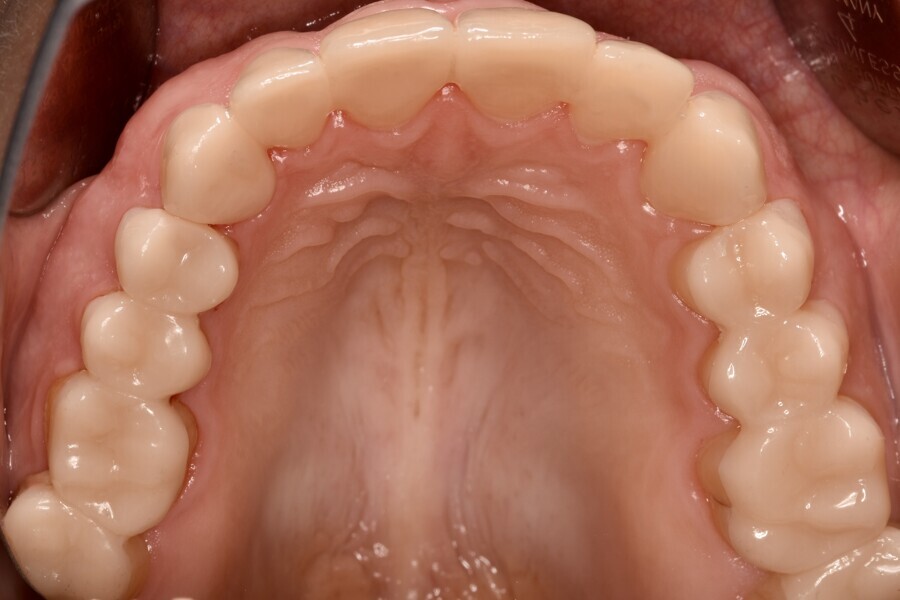

Fig. 1d: Almost complete loss of the occlusal relief in the upper jaw.

The clinical and radiographic examination revealed pronounced erosive defects on all teeth (Figs. 1a-f). To prevent nocturnal wear of the remaining tooth structure, an occlusal splint had been prepared by the patient’s general dentist in the past. Quick screening for temporomandibular disorder using the tool developed by the German Society of Craniomandibular Function and Disorders was carried out and revealed no functional abnormalities. The diagnosis was generalised, highly pronounced erosion due to exogenous acid (cola), abrasion and attrition with decreased OVD, multiple carious lesions, dentine hypersensitivity, gingivitis and compromised aesthetics.